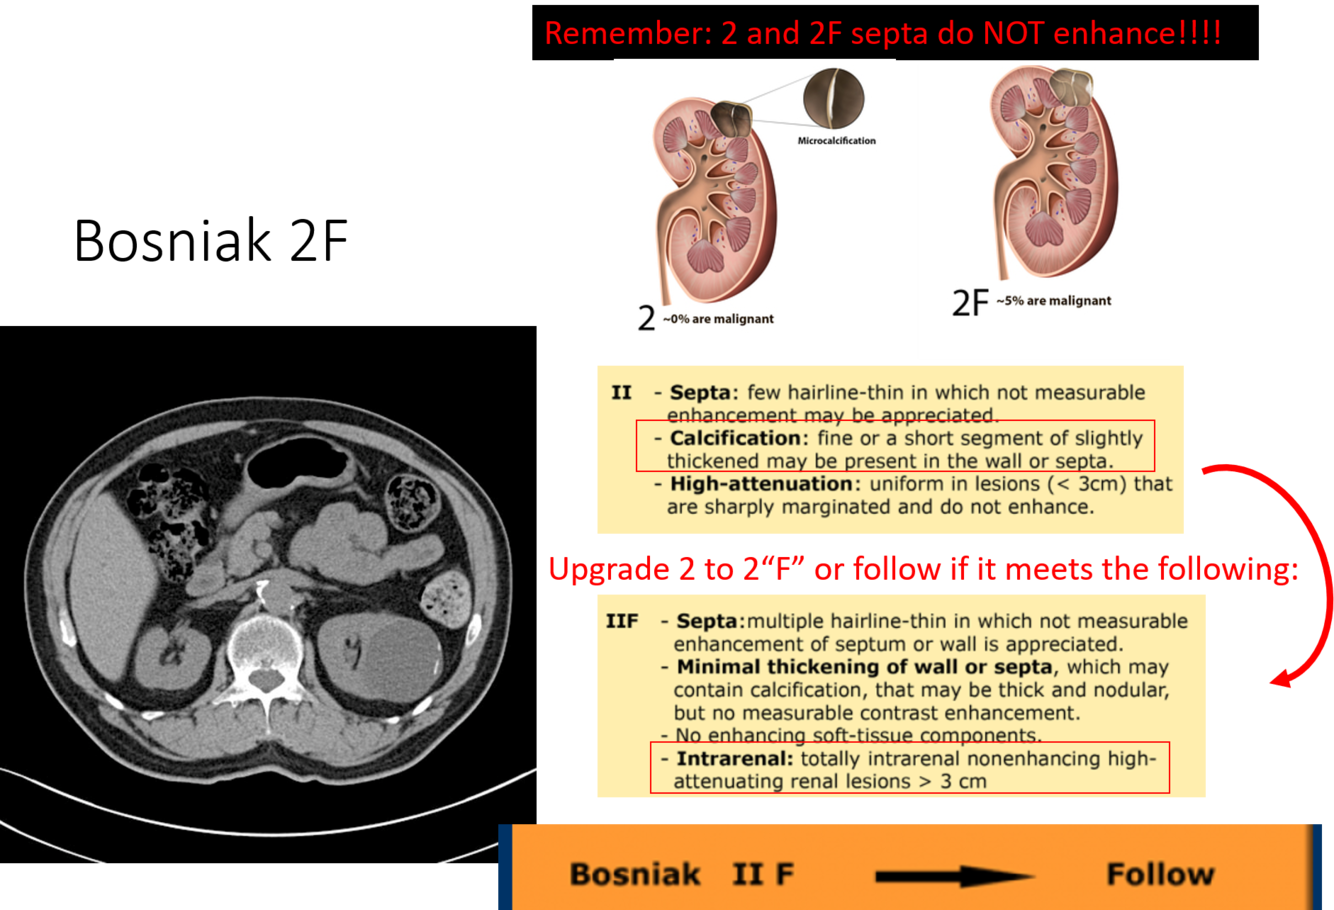

what bosniak classification do you follow?

bosniak 2F

which bosniak classifications do you excise?

3 and 4